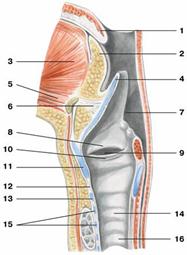

Рис. Дыхательный аппарат:

1 — полость носа; 2 — глотка;

3 — полость рта; 4 — надгортанный хрящ;

5 — складка преддверия; 6 — желудочек гортани;

7 — голосовая складка; 8 — щитовидный хрящ;

9 — гортань; 10 — трахея;

11 — раздвоения трахеи; 12 — главный правый бронх;

13 — главный левый бронх; 14 — верхняя доля правого легкого;

15 — верхняя доля левого легкого; 16 — средняя доля правого легкого;

17 — нижняя доля левого легкого; 18 — нижняя доля правого легкого